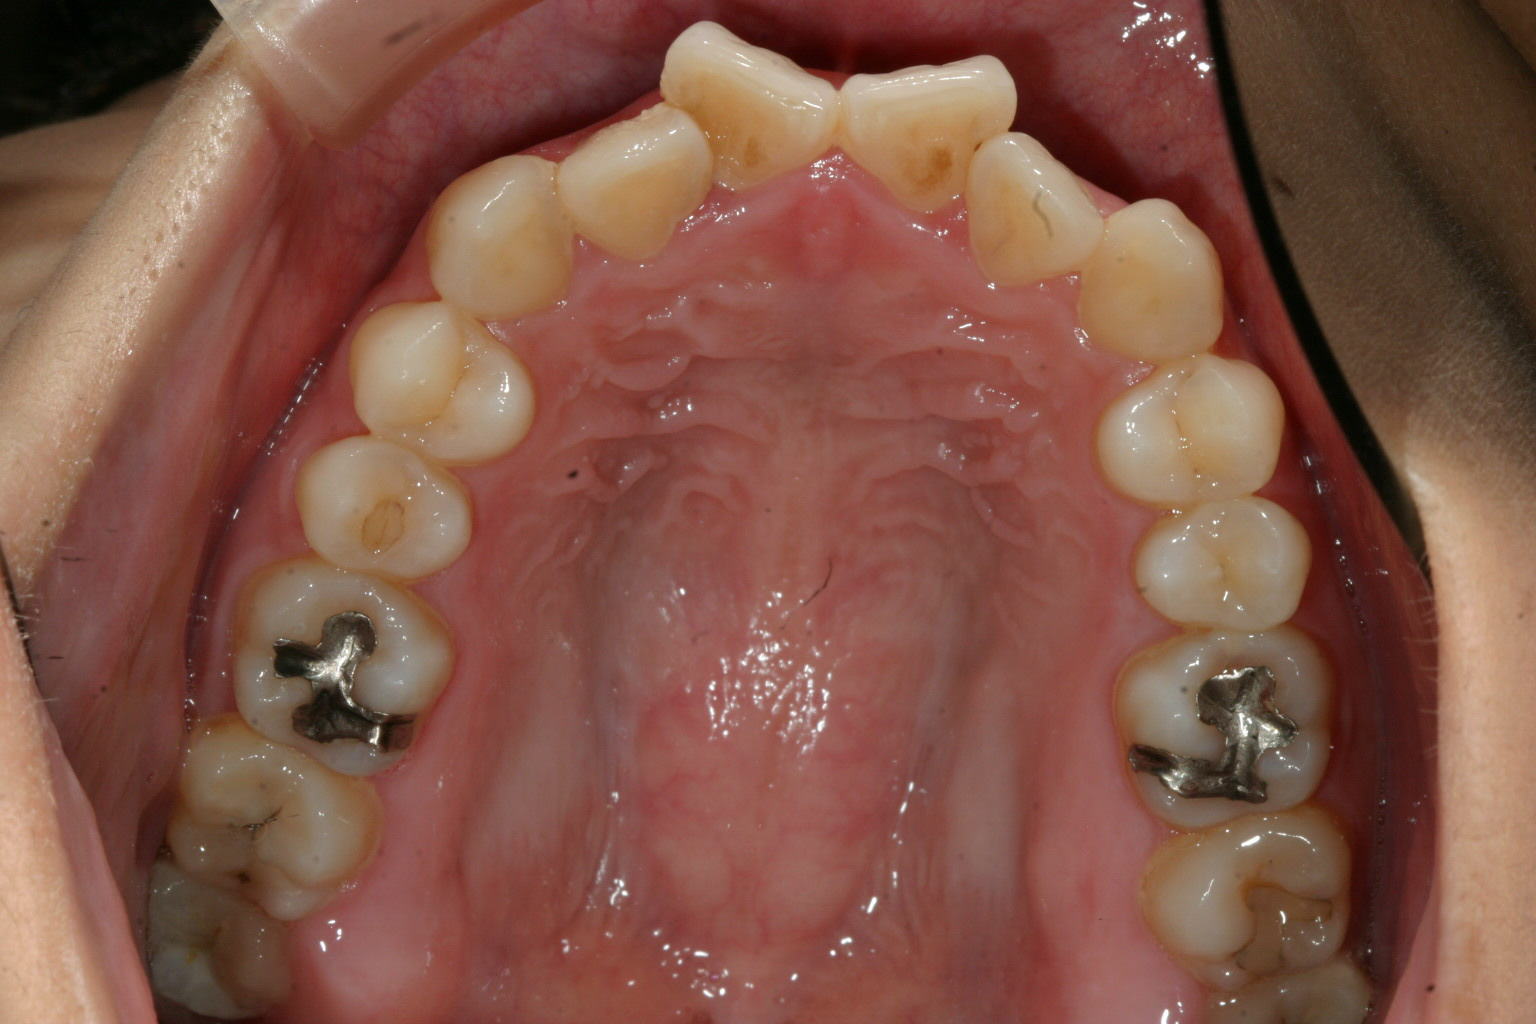

かなりキツイ翼状捻転です。犬歯間幅径が狭いです。

典型的な犬歯間幅径が狭い為の叢生(翼状捻転)です。

犬歯間を広げることで簡単に改善出来ます。